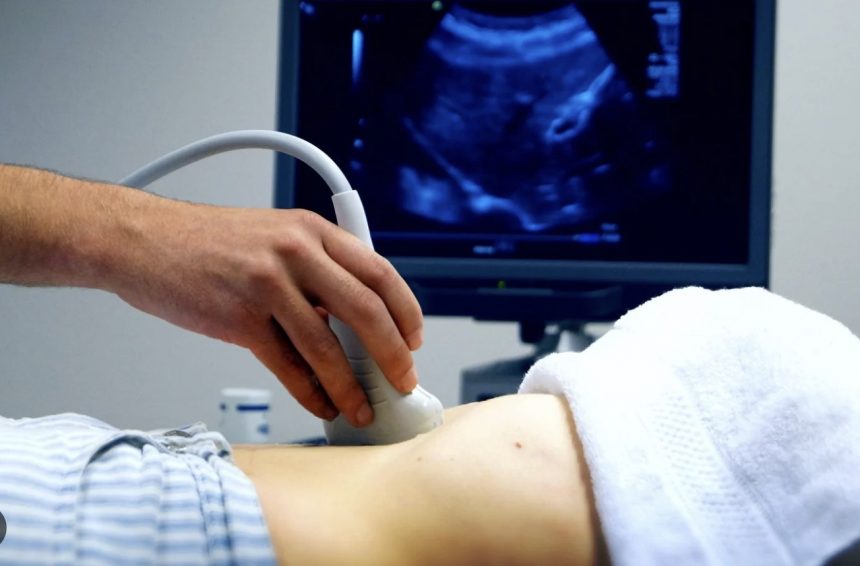

Регулярне проведення УЗД обстеження є важливим елементом профілактики та своєчасного виявлення захворювань, що дозволяє розпочати лікування на ранніх стадіях і значно підвищити ефективність терапії.

УЗД — це неінвазивний метод дослідження, який не використовує іонізуючого випромінювання, на відміну від рентгенівських методів. Це робить його безпечним для пацієнтів, включаючи вагітних жінок та дітей. Крім того, багато медичних установ пропонують пільгові умови для соціально незахищених категорій населення, таких як пенсіонери, що робить процедуру доступною для широкого кола осіб.